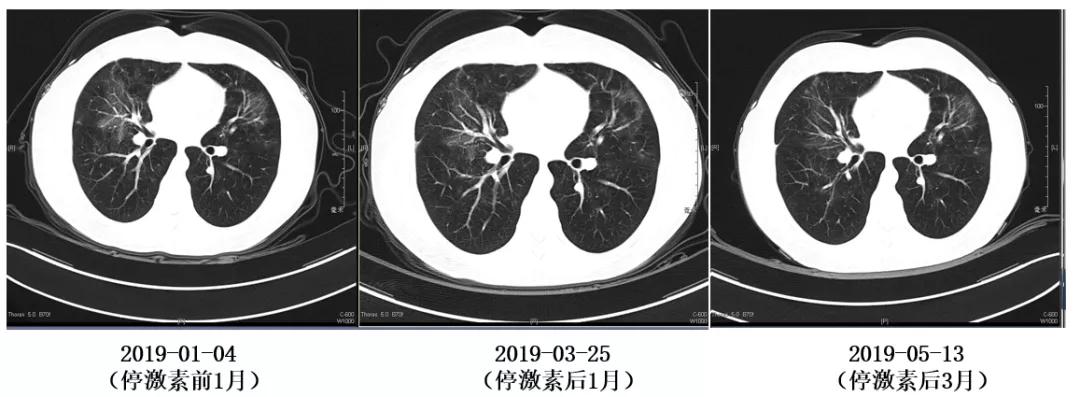

随访胸部影像学:

停药后随访情况:

2019-02-06 起停用药物。

2019-03-25 复查胸部CT,提示两肺病灶较停药前有所增多。考虑患者目前无明显咳嗽咳痰,胸闷,气促不适,炎症指标均正常,已停用激素1月余,嘱患者暂继续观察。

2019-05-13 胸部CT示「机化性肺炎」治疗后复查,与 2019-03-25片相比两上肺病变部分稍进展,余较前相仿。

随访胸部影像: 2019-5-13胸部CT见肺部阴影增多。